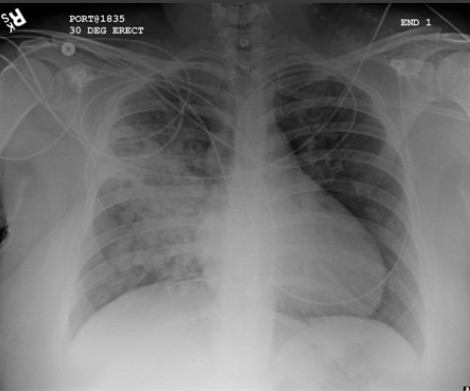

Considere uma tomografia computadorizada de tórax ou outras investigações de imagem para pneumonia “complicada” ou alterações atípicas em uma radiografia torácica, como cavitação, padrão de consolidação multifocal ou derrame pleural.[89][Figure caption and citation for the preceding image starts]: Radiografia de tórax mostrando pneumonia cavitando no lobo superior esquerdoDa coleção do Dr. Jonathan Bennett. Usado com permissão [Citation ends].

[Figure caption and citation for the preceding image starts]: Opacificação aumentada da região peri-hilar direita e do segmento superior dos lobos inferior e superior direitos, compatível com agravamento da pneumonia por aspiraçãoDa coleção do Dr. Roy Hammond. Usado com permissão [Citation ends].